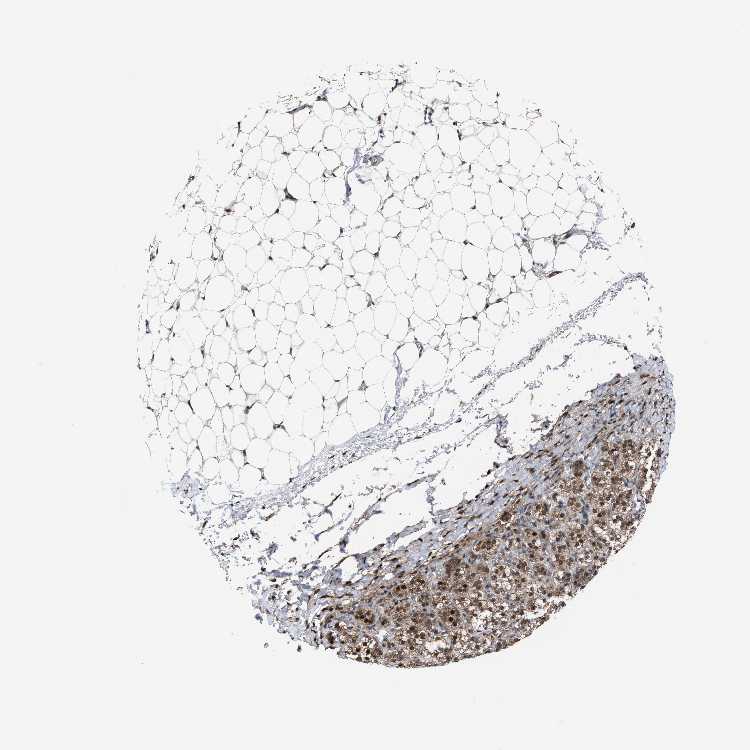

ADRENAL GLAND - Antibody stainingi

Antibody staining in the annotated cell types in the current human tissue is reported as not detected, low, medium, or high, based on conventional immunohistochemistry profiling in selected tissues. This score is based on the combination of the staining intensity and fraction of stained cells.

Each image is clickable and will lead to virtual microscopy that enables deeper exploration of all samples and also displays staining intensity scores, fraction scores and subcellular localization as well as patient and tissue information for each sample.

Antibody HPA021603

Glandular cells Medium